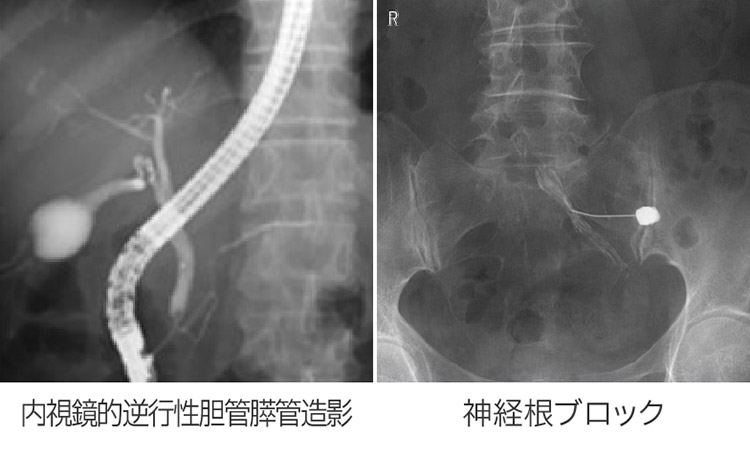

消化管(食道・胃・十二指腸・大腸)、泌尿器(腎臓・尿管・膀胱・尿道)、整形(脊髄腔・神経根ブロック・整復)、産婦人科(子宮・卵管)など各診療科のさまざまな検査や治療が行われます。

X線TV検査画像